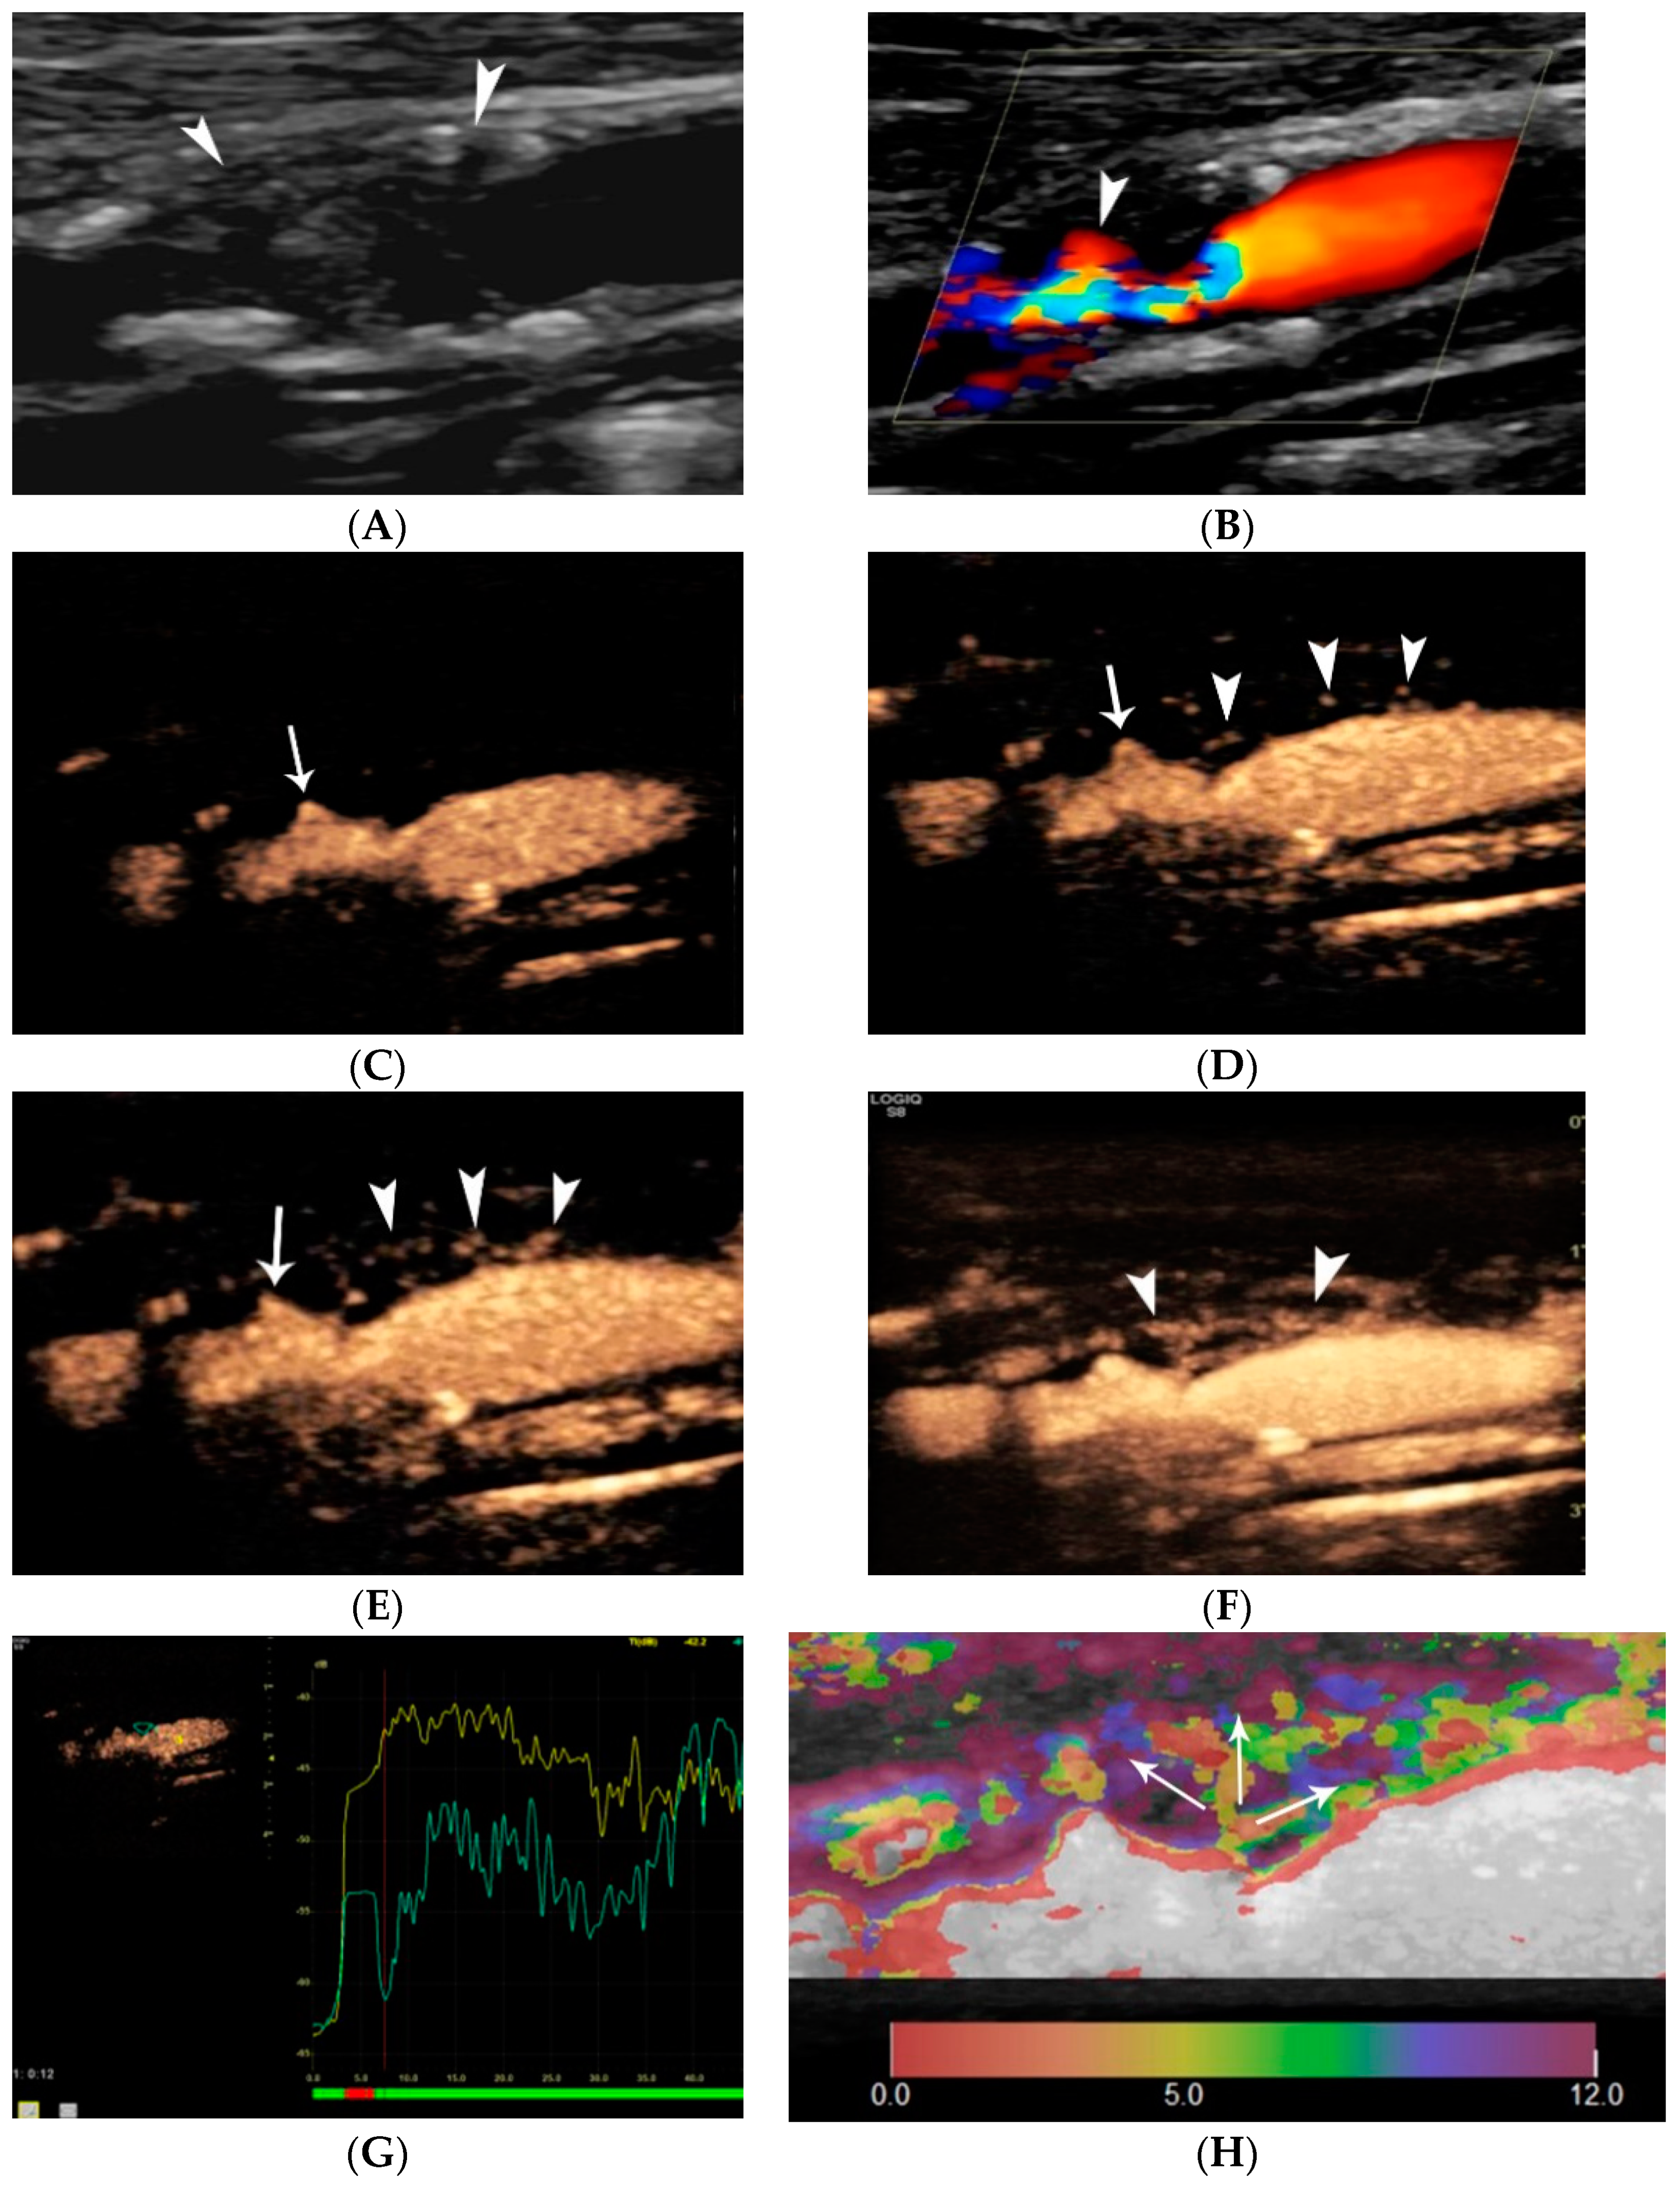

4.1.4. Plaque Ulceration

- Rafailidis, V.; Chryssogonidis, I.; Tegos, T.; Kouskouras, K.; Charitanti-Kouridou, A. Imaging of the ulcerated carotid atherosclerotic plaque: A review of the literature. Insights Imaging 2017, 8, 213–225. [Google Scholar] [CrossRef]

- Rafailidis, V.; Charitanti, A.; Tegos, T.; Rafailidis, D.; Chryssogonidis, I. Swirling of microbubbles: Demonstration of a new finding of carotid plaque ulceration on contrast-enhanced ultrasound explaining the arterio-arterial embolism mechanism. Clin. Hemorheol. Microcirc. 2016, 64, 245–250. [Google Scholar] [CrossRef]

- Rafailidis, V.; Chryssogonidis, I.; Xerras, C.; Nikolaou, I.; Tegos, T.; Kouskouras, K.; Rafailidis, D.; Charitanti-Kouridou, A. A comparative study of color Doppler imaging and contrast-enhanced ultrasound for the detection of ulceration in patients with carotid atherosclerotic disease. Eur. Radiol. 2019, 29, 2137–2145. [Google Scholar] [CrossRef]

- Lyu, Q.; Tian, X.; Ding, Y.; Yan, Y.; Huang, Y.; Zhou, P.; Hui, P. Evaluation of Carotid Plaque Rupture and Neovascularization by Contrast-Enhanced Ultrasound Imaging: An Exploratory Study Based on Histopathology. Transl. Stroke Res. 2021, 12, 49–56. [Google Scholar] [CrossRef]